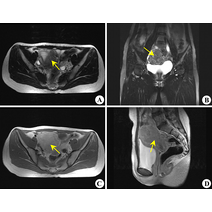

[最佳答案] 腺肌瘤一般是指子宫腺肌症,患者会出现痛经、月经量增多等月经失调症状,对女性生育功能影响比较大,可能会导致不孕症,需要针对不同情况采取治疗方法。腺肌瘤是一种由于黏膜层组织异位到子宫肌层,而产生的一种瘤样良性疾病,近年来由于剖宫产、流产率上升,此疾病的发生率也有逐年上升趋势,临床上多采用药物治疗、手术治疗、期待治疗等。 1、期待治疗:指的是无需进行治疗,定期进行检查腺肌瘤的生长,观察病情进展情况,常适合临近绝经的患者; 2、药物治疗:常用的药物有桂枝茯苓胶囊、宫瘤消胶囊、逍遥丸等中成药,但起效较慢,可能效果并不明显,主要针对较小的子宫肌瘤。也可以服用抗宫炎片或激素类药物,如戈舍瑞林、亮丙瑞林、米非司酮等抑制子宫肌瘤生长,但不可擅自服用,还可以进行局部药物治疗,如促性腺激素抑制激素或左快诺孕酮宫内缓释系统治疗,建议在医生指导下结合个人情况选择药物; 3、手术治疗:建议定期到医院复查,密切观察肌瘤的生长情况,如果肌瘤生长过快,需要采用手术治疗。根据个人情况采取根治性全子宫切除术、子宫腺肌瘤切除、子宫肌层电凝术、子宫内膜及肌层切除术、子宫动脉阻断术等手术方式,其中全子宫切除术适用于无生育要求的患